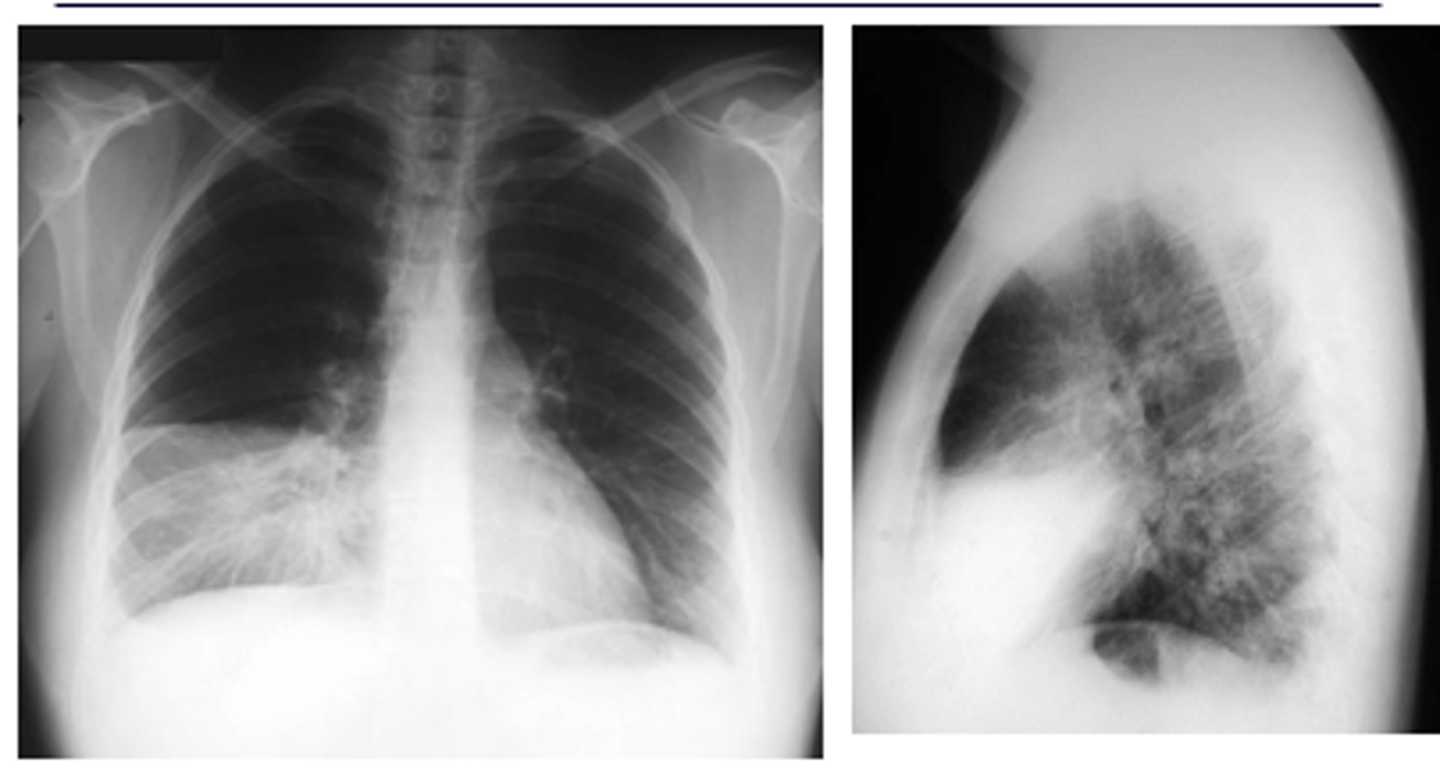

ID sign on back and finding

RML pneumonia obscuring the cardiac border but not the R hemidiaphragm. Note the triangular density on the lateral view.

<p>RML pneumonia obscuring the cardiac border but not the R hemidiaphragm. Note the triangular density on the lateral view.</p>